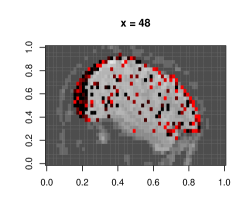

This dataset is due to Wakeman & Henson (2015), where each of the 19 subjects go through 9 runs of consecutive visual tasks. Blood oxygen level readings are recorded across time as 3D images made of (total 135,168) voxels. Here we use the data from a single run and task on subject 1, and aim to estimate dependence patterns of readings across 210 time points and areas of the brain.

We fit separate regressions at each voxel (Appendixย E), with second order autoregressive terms, neighboring voxel readings and one-hot encoded visual task categories in the design matrix. After applying the e-value feature selection, we compute the F-statistic at each voxel using selected coefficients only, and obtain their p-values. Fig.ย 7.1c highlights voxels with p-values . Left and right visual cortex areas show high spatial dependence, with more dependence on the left side. Signals from the right visual field obtained by both eyes are processed by the left visual cortex. The lop-sided dependence pattern suggests that visual signals from the right side led to a higher degree of processing in our subjectโs brain. We also see activity in the cerebellum, the role of which in visual perception is well-known (Calhoun etย al., 2010; Kirschen etย al., 2010).

Appendix E Details of fMRI data implementation

Typically, the brain is divided by a grid into three-dimensional array elements called voxels, and activity is measured at each voxel. More specifically, a series of three-dimensional images are obtained by measuring Blood Oxygen Level Dependent (BOLD) signals for a time interval as the subject performs several tasks at specific time points. A single fMRI image typically consists of voxels in the order of , which makes even fitting the simplest of statistical models computationally intensive when it is repeated for all voxels to generate inference, e.g. investigating the differential activation of brain region in response to a task.

The dataset we work with comes from a recent study involving 19 test subjects and two types of visual tasks (Wakeman & Henson, 2015). Each subject went through 9 runs, in which they were showed faces or scrambled faces at specific time points. In each run 210 images were recorded in 2 second intervals, and each 3D image was of the dimension of , which means there were 135,168 voxels. Here we use the data from a single run on subject 1, and perform a voxelwise analysis to find out the effect of time lags and BOLD responses at neighboring voxels on the BOLD response at a voxel. Formally we consider separate models at voxel , with observations across time points .

Clubbing together the stimuli, drift, neighbor and autoregressive terms into a combined design matrix and coefficient vector , we can write . We estimate the set of non-zero coefficients in using the e-value method. Suppose this set is , and its subsets containing coefficient corresponding to neighbor and non-neighbor (i.e. stimuli and drift) terms are and , respectively. To quantify the effect of neighbors we now calculate the corresponding -statistic:

and obtain its -value, i.e. .

Figureย E.1 shows plots of the voxels with a significant -value from the above -test, with a darker color associated with lower p-value, as opposed to the smoothed surface in the main paper. Most of the significant terms were due to the coefficients corresponding to neighboring terms. A very small proportion of voxels had any autoregressive effects selected (less than 1%), and most of them were in regions of the image that were outside the brain, indicating noise.